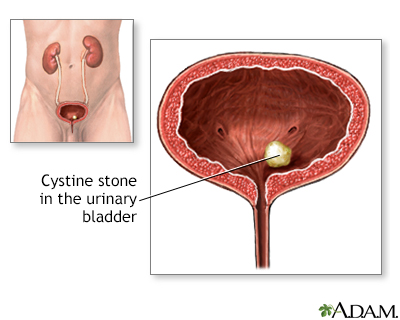

How to know if you have kidney stones discount, Symptoms of Kidney Stones discount

Signs You May Have Kidney Stones Blog Loyola Medicine- how to know if you have kidney stones